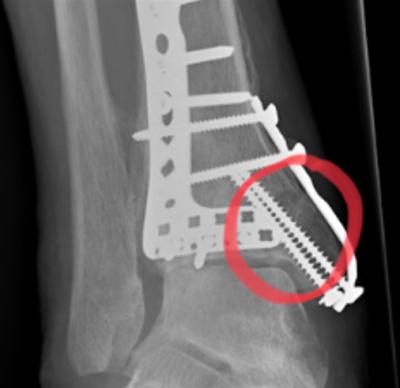

De botbreuk ontstond in december 2023 en na 9 à 10 maanden was er nog steeds geen zichtbare botaanmaak. Eind oktober zijn we gestart met lasertherapie en binnen slechts 4 weken was de botbreuk volledig hersteld!

Op 25 oktober zijn we gestart met lasertherapie voor deze botbreuk, die na 10 maanden nog geen zichtbare botaanmaak liet zien. Dankzij een effectief behandelprotocol en de krachtige werking van lasertherapie was de breuk binnen 4 weken volledig hersteld!

Herstel na een botbreuk 19-12-2023 Voor Herstel na een botbreuk Tussen Herstel na een botbreuk 25-11-2024 Na

De orthopeed wilde bij de laatste controle geen röntgenfoto maken, maar Jessie zorgde ervoor dat ik ergens anders een foto kon laten maken om het volledige herstel te bevestigen. Deze foto's heb ik met blijdschap kunnen tonen aan de arts omdat mijn botbreuk volledig hersteld is. Nu kan eindelijk het plaatwerk eruit, en ik ben zó opgelucht!"